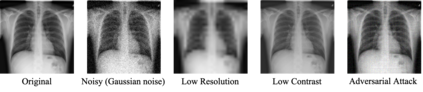

While deep learning models have achieved remarkable success across a range of medical image analysis tasks, deployment of these models in real clinical contexts requires that they be robust to variability in the acquired images. While many methods apply predefined transformations to augment the training data to enhance test-time robustness, these transformations may not ensure the model's robustness to the diverse variability seen in patient images. In this paper, we introduce a novel three-stage approach based on transformers coupled with conditional diffusion models, with the goal of improving model robustness to the kinds of imaging variability commonly encountered in practice without the need for pre-determined data augmentation strategies. To this end, multiple image encoders first learn hierarchical feature representations to build discriminative latent spaces. Next, a reverse diffusion process, guided by the latent code, acts on an informative prior and proposes prediction candidates in a generative manner. Finally, several prediction candidates are aggregated in a bi-level aggregation protocol to produce the final output. Through extensive experiments on medical imaging benchmark datasets, we show that our method improves upon state-of-the-art methods in terms of robustness and confidence calibration. Additionally, we introduce a strategy to quantify the prediction uncertainty at the instance level, increasing their trustworthiness to clinicians using them in clinical practice.